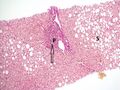

Micrograph showing cirrhosis, trichrome stain

The gold standard for diagnosis of cirrhosis is a liver biopsy. This is usually carried out as a fine-needle approach, through the skin (percutaneous), or internal jugular vein (transjugular).[80] Endoscopic ultrasound-guided liver biopsy (EUS), using the percutaneous or transjugular route, has become a good alternative to use.[81][80] EUS can target liver areas that are widely separated,[82] and can deliver bi-lobar biopsies.[81] A biopsy is not necessary if the clinical, laboratory, and radiologic data suggest cirrhosis. Furthermore, a small but significant risk of complications is associated with liver biopsy, and cirrhosis itself predisposes for complications caused by liver biopsy.[83]

Once the biopsy is obtained, a pathologist will study the sample. Cirrhosis is defined by its features on microscopy: (1) the presence of regenerating nodules of hepatocytes and (2) the presence of fibrosis, or the deposition of connective tissue between these nodules. The pattern of fibrosis seen can depend on the underlying insult that led to cirrhosis. Fibrosis can also proliferate even if the underlying process that caused it has resolved or ceased. The fibrosis in cirrhosis can lead to destruction of other normal tissues in the liver: including the sinusoids, the space of Disse, and other vascular structures, which leads to altered resistance to blood flow in the liver, and portal hypertension.[84]

As cirrhosis can be caused by many different entities which injure the liver in different ways, cause-specific abnormalities may be seen. For example, in chronic hepatitis B, there is infiltration of the liver parenchyma with lymphocytes.[84] In congestive hepatopathy there are erythrocytes and a greater amount of fibrosis in the tissue surrounding the hepatic veins.[86] In primary biliary cholangitis, there is fibrosis around the bile duct, the presence of granulomas and pooling of bile.[87] Lastly in alcoholic cirrhosis, there is infiltration of the liver with neutrophils.[84]

Macroscopically, the liver is initially enlarged, but with the progression of the disease, it becomes smaller. Its surface is irregular, the consistency is firm, and if associated with steatosis the color is yellow. Depending on the size of the nodules, there are three macroscopic types: micronodular, macronodular, and mixed cirrhosis. In the micronodular form (Laennec's cirrhosis or portal cirrhosis), regenerating nodules are under 3 mm. In macronodular cirrhosis (post-necrotic cirrhosis), the nodules are larger than 3 mm. Mixed cirrhosis consists of nodules of different sizes.[88]